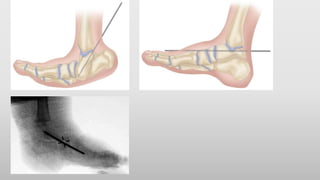

• TA lengethening- percutaneous TA lengethening

- Z lengthening

• Gastrocnemius recession

Tendoachillies lengethening is a safe procedure when used in conjunction of

hindfoot fusion procedures for flatfoot deformities